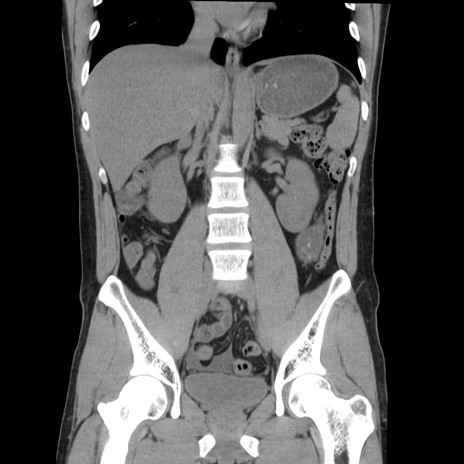

症例36(冠状断像)

【症例】20歳代 男性

【主訴】心窩部痛

【現病歴】今朝より上腹部痛あり。一旦軽快していたが再度出現したため救急要請。昨日夕に白身の魚を含む刺身を食べた。

【身体所見】BP 136/89mmHg、HR 74/min、BT 37.0℃、腹部:膨満、軟、心窩部に圧痛あり。反跳痛なし、筋性防御なし、腸雑音やや亢進あり。

【データ】WBC 17700、CRP 0.48